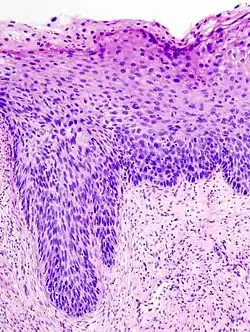

Histologicznie CIN manifestuje się zaburzeniem różnicowania komórek nabłonka wielowarstwowego płaskiego, zmianą morfologii pojedynczych komórek i zaburzeniem budowy architektonicznej całego nabłonka. Komórki prawidłowego nabłonka mają okrągłe, równe jądra o drobnoziarnistej chromatynie rozproszonej regularnie. W nabłonku z cechami neoplazji śródnabłonkowej (CIN) stwierdza się cechy atypii: powiększenie jąder komórkowych, ich hiperchromazję, polimorfizm kształtu, wielkości oraz zabarwienia. Częste są komórki dwu- i wielojądrowe. Organizacja nabłonka jest zaburzona. W miarę nasilenia zmian morfologicznych wzrasta stopień CIN jaki przypisuje się tym zmianom. Ponadto, w komórkach nabłonka zainfekowanego wirusem brodawczaka stwierdza się koilocyty – komórki z dużą jasną wodniczką, silnie zaznaczoną hiperchromazją i charakterystycznym, "pomarszczonym" obrysem. W zainfekowanym HPV nabłonku występuje parakeratoza, a granice międzykomórkowe są wyraźnie widoczne i pogrubiałe. Komórki nabłonka z cechami CIN często "tapetują" cewki gruczołowe, co należy w ocenie histologicznej różnicować z naciekaniem podścieliska.

| CIN I | CIN II | CIN III |

| Proliferacja niedojrzałych komórek ograniczona do dolnej 1/3 nabłonka Zachowana polarność komórek we wszystkich warstwach Nieliczne mitozy u podstawy nabłonka Niewielki polimorfizm jąder komórkowych Może być obecna koilocytoza |

Proliferacja niedojrzałych komórek ograniczona do dolnych 2/3 nabłonka Komórki warstw powierzchownych wykazują cechy dojrzewania obecny polimorfizm jąder komórkowych |

Niedojrzałe komórki na całej wysokości nabłonka Nabłonek pogrubiały, wzrost komórkowości Całkowicie zaburzona architektura nabłonka Liczne, często patologiczne mitozy Nierzadko wybitny polimorfizm jąder komórkowych |